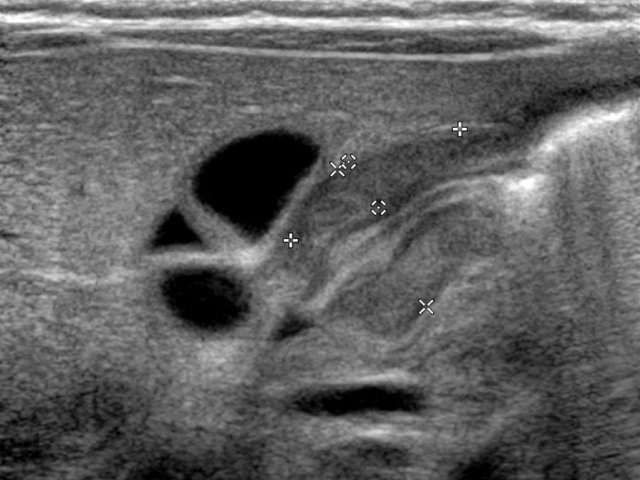

Hypertrophic pyloric stenosis

Projectile vomiting is the key feature in patients with hypertrophic pyloric stenosis.

The cause of the muscle hypertrophy which causes the gastric outlet obstruction is unknown.

There is a familial predisposition and it is more common in boys.

Hypertrophic pyloric stenosis typically presents after the neonatal period, at the age of 4-8 weeks.

However early presentation can also occur.

Ultrasound in a fasting child will show retained fluid in the stomach. There is no passage along the hypertrophic pyloric muscle.

For optimal viewing the child must be positioned right side down and if the stomach is empty it should be filled by drinking Pedialyte or glucose solution during the examination.

If the stomach is too full, the child can be placed on the left side to help the pylorus to move anteriorly.

The transversal diameter of the single muscle wall is the most reliable measurement to diagnose pyloric muscle hypertrophy.

A measurement of more than 3 mm on a transverse image indicates hypertrophy.

A transverse total diameter more than 14 mm and a total length of the pyloric canal more than 15 mm support the diagnosis.

- Single muscle wall > 3mm

- Total transverse diameter > 14mm

- Length pyloric canal > 15mm